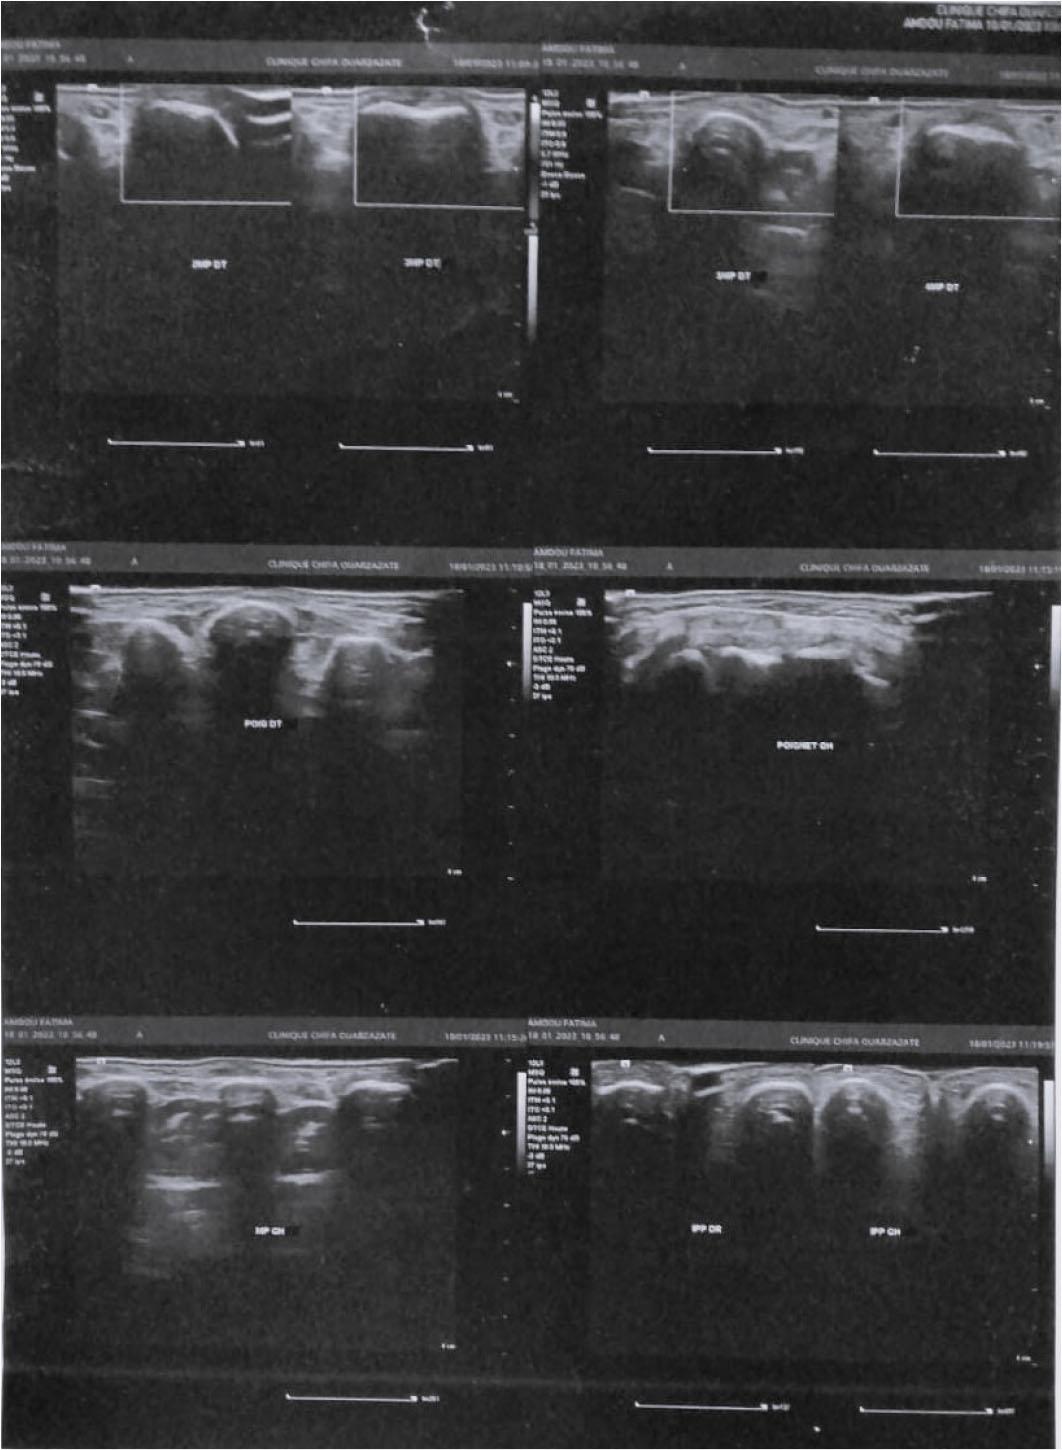

Joint ultrasound of both wrists, hands, and the right elbow with no notable abnormalities.